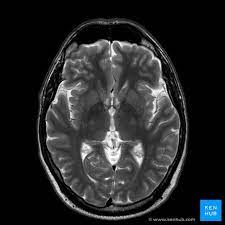

Brain MRI, or Magnetic Resonance Imaging, is a non-invasive procedure that provides detailed images of the brain. It's a crucial tool in diagnosing various neurological conditions, offering a window into the mind's complex workings. For Priya, this advanced technology was not just about diagnosing a condition—it was about reclaiming her life, free from the shackles of uncertainty.

The day of the MRI, Priya's heart raced with a mix of fear and hope. As she lay still, listening to the rhythmic hum of the machine, she realized this was a pivotal moment. The results, when they came, were both a relief and a revelation. The MRI revealed a benign cyst causing her symptoms, something that could be treated with medication and lifestyle adjustments.